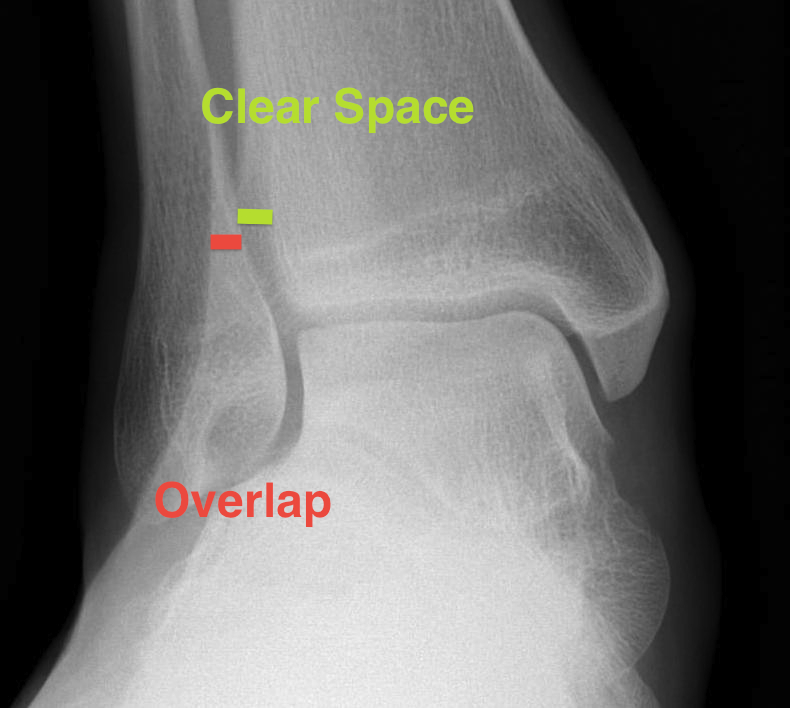

Increased tibio-fibular clear space  Overlap Increased medial clear space

Medial border of the fibula

Lateral border of the posterior tibia (incisura fibularis)

Measured 1 cm above the plafond

Overlap of the fibula and the anterior tibial tubercle

Medial talus to lateral medial malleolus

<5mm AP and mortise

> 6 mm AP view

> 1 mm mortise view

< 4mm

Equal to superior clear space

Syndesmotic injury Syndesmotic injury

Deltoid ligament injury

Lateral talar shift

Ankle AP Xray Syndesmotic Measurements Ankle Mortice Xray Syndesmotic Measurements Mortise

Lateral talar shift / increased medial clear space / deltoid ligament injury

Ankle Fracture Increased Medial Clear SpaceAnkle Fracture Increased Medial Clear Space 2Maisonnerve